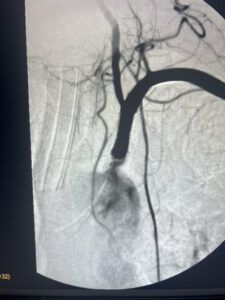

αποκατάσταση με τοποθέτηση stent

σε 24 ώρες εξιτήριο